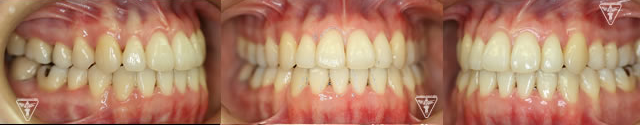

20代女性:オープンバイト(開咬)をゴムメタルにて矯正治療したケース

治療前後の比較

治療前、装置装着直後

治療後

保定装置の装着

長期安定と後もどり防止のために、保定装置を装着します。

長谷川 信先生考案のフロッシュ装置(ゴムメタル使用)を夜間装置します。